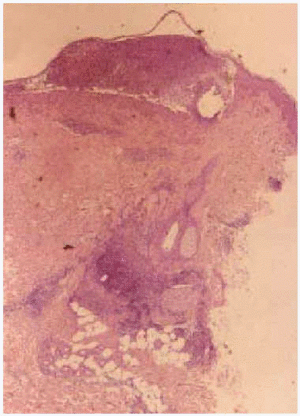

Se realizó biopsia de una de las lesiones, que mostró la existencia de una ligera acantosis de la epidermis y la presencia de pústulas subcórneas, junto con un moderado infiltrado inflamatorio de tipo mixto en la dermis superior (fig. 3). En la inmunofluorescencia directa se observaba depósito de IgA y C3 entre las células epidémicas subcórneas (fig. 4). La inmunofluorescencia indirecta fue negativa.

Fig. 3.--Ligera acantosis de la epidermis, con pústula subcórnea e infiltrado inflamatorio mixto en dermis superficial.